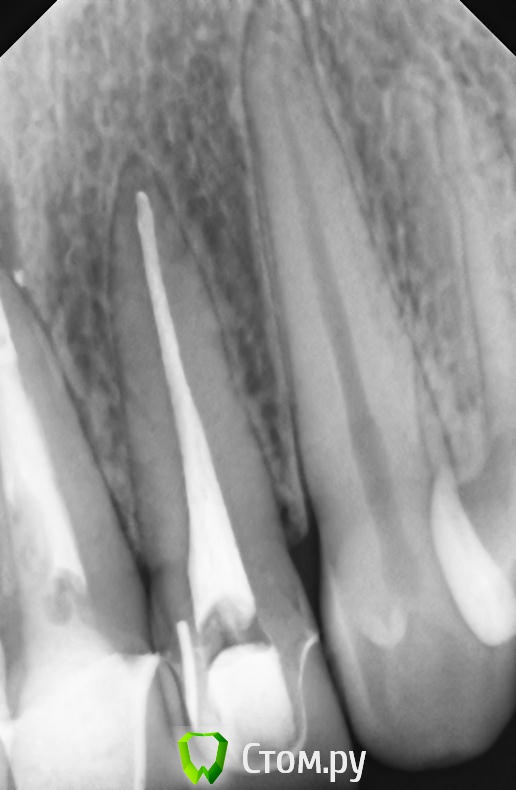

markoFFka Опубликовано 22 ноября, 2013 Автор Поделиться Опубликовано 22 ноября, 2013 Перелома нет? Есть сомнения по снимкуну меня этот же вопрос собственно и интересует.но на двойке с другой стороны,как мне кажется,тоже подобные полосы.вот снимок 12. Ссылка на комментарий

markoFFka Опубликовано 23 ноября, 2013 Автор Поделиться Опубликовано 23 ноября, 2013 (изменено) Да,конечно пародонт)21 на снимке в девятом сообщении есть вместе с 11 и 12. 11 и 21 лечены очень много лет назад,никогда не беспокоили.отдельный снимок 11 и 12 делали летом,сейчас не могу выложить.в данном случае точно не они.Перкуссия положительна именно 22го. Изменено 23 ноября, 2013 пользователем markoFFka Ссылка на комментарий

Kivilgar Опубликовано 23 ноября, 2013 Поделиться Опубликовано 23 ноября, 2013 Да,конечно пародонт)21 на снимке в девятом сообщении есть вместе с 11 и 12. 11 и 21 лечены очень много лет назад,никогда не беспокоили.отдельный снимок 11 и 12 делали летом,сейчас не могу выложить.в данном случае точно не они.Перкуссия положительна именно 22го.Тогда только и остается http://s57.radikal.ru/i156/1311/fd/209d7896d0be.jpg 6 Ссылка на комментарий